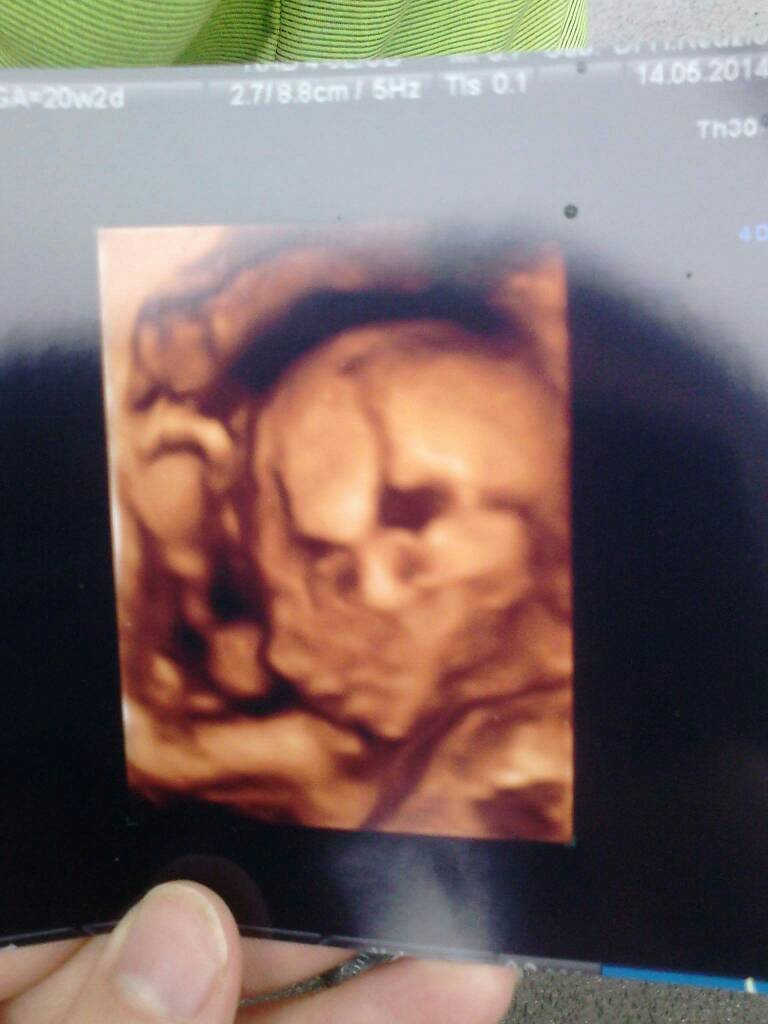

Moja w 16tc

I 20tc

1491820713-aaaaaa.jpeg

1491820721-aaaaaa.jpeg